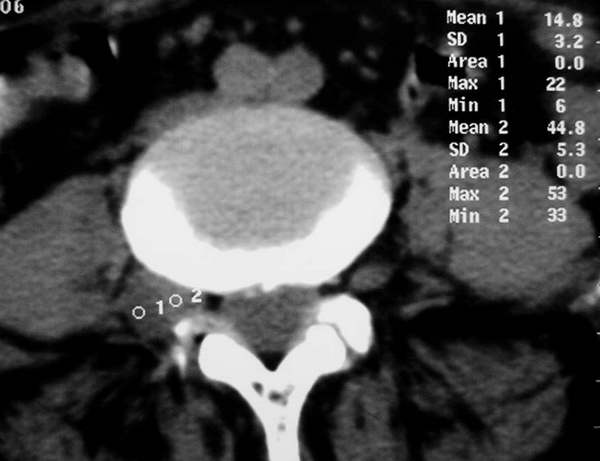

标题: CT3877:神经纤维瘤 [打印本页]

标题: CT3877:神经纤维瘤

女:67岁,右下肢疼痛20余年。

行腰椎间盘扫描。

右侧椎间孔外侧见类圆形软组织肿块边缘清与右神经根关系密切

考虑神经鞘瘤

此患者外院手术病理为:神经纤维瘤。在外院做mri平扫+增强,至今没照到mri图像感到遗憾。如果什么时间借到片子一定照下来传给大家。